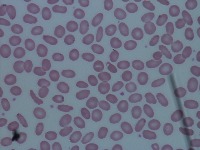

Medical Diagnosis and Research: The "New-Chula" model could be used in medical laboratories and hospitals to automatically identify and classify different cell types in blood samples. This could assist in diagnosing various blood disorders or diseases such as anemia or leukemia, thereby speeding up analysis and treatment processes.

Education and Training: The model could serve as an educational tool for medical students or professionals in training. By using this model, they could learn to identify various types of cells more quickly and accurately, enhancing their understanding of hematology.

Pharmaceutical Trials: During drug testing and development, pharmaceutical companies may use this model to analyze the impact of drugs on different cell types in order to assess effectiveness or side effects.

Public Health Monitoring: Governments and public health organizations could use it to monitor the health condition of the general population, potentially detecting the early stages of an outbreak or epidemic.

Biotechnology Industry: Biotech firms or research labs may use this model for particular research projects involving genetic modification or cellular biology studies where identification and classification of different cell types is necessary.